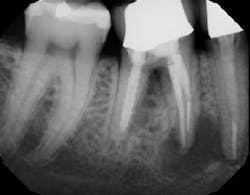

In summation, the best treatment for nerve injury continues to be prevention. If there is any doubt by the treating clinician as to the proximity of an odontogenic lesion to the nerve space (figure 4), a CT scan prior to extraction therapy is the gold standard of care (figure 5). This pretreatment diagnostic can avoid both clinical and legal headaches.

Figure 4: Another case demonstrating periapical pathology and its proximity to the IAN